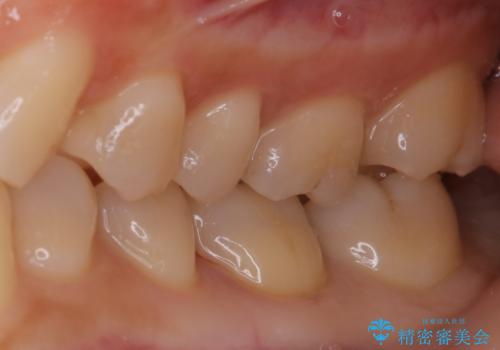

適合のよいセラミックで自分の歯となじむ自然な仕上がりに

- 大きく口を開けると目立つ銀歯のやり替えをご希望された患者様です。適合のよいセラミックインレーで補綴することで、将来的な虫歯発生のリスクを最小限に抑え、機能面でも安心して使っていただけるようにしました

自費診療で用いられる材料は保険適応の材料に比べて、より精密で適合の良い被せ物作ることができるため、長期的な虫歯のリスクを大幅に減らすことが可能です。